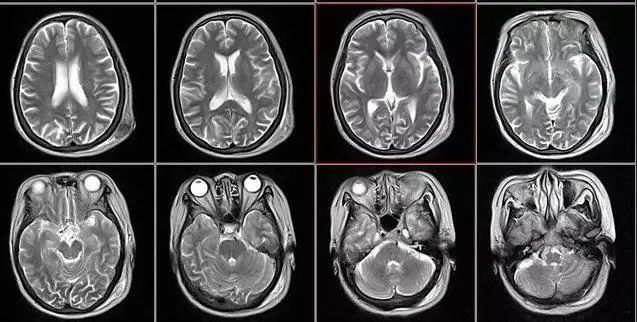

2、颈椎腰椎——最佳选核磁、次选CT

颈椎病、腰椎间盘突出等椎间盘疾病需要观察椎间盘与相应的神经根,要想更好观察这些软组织,最优选择就是核磁。同样,对于关节、肌肉、脂肪组织检查,核磁也是首选。